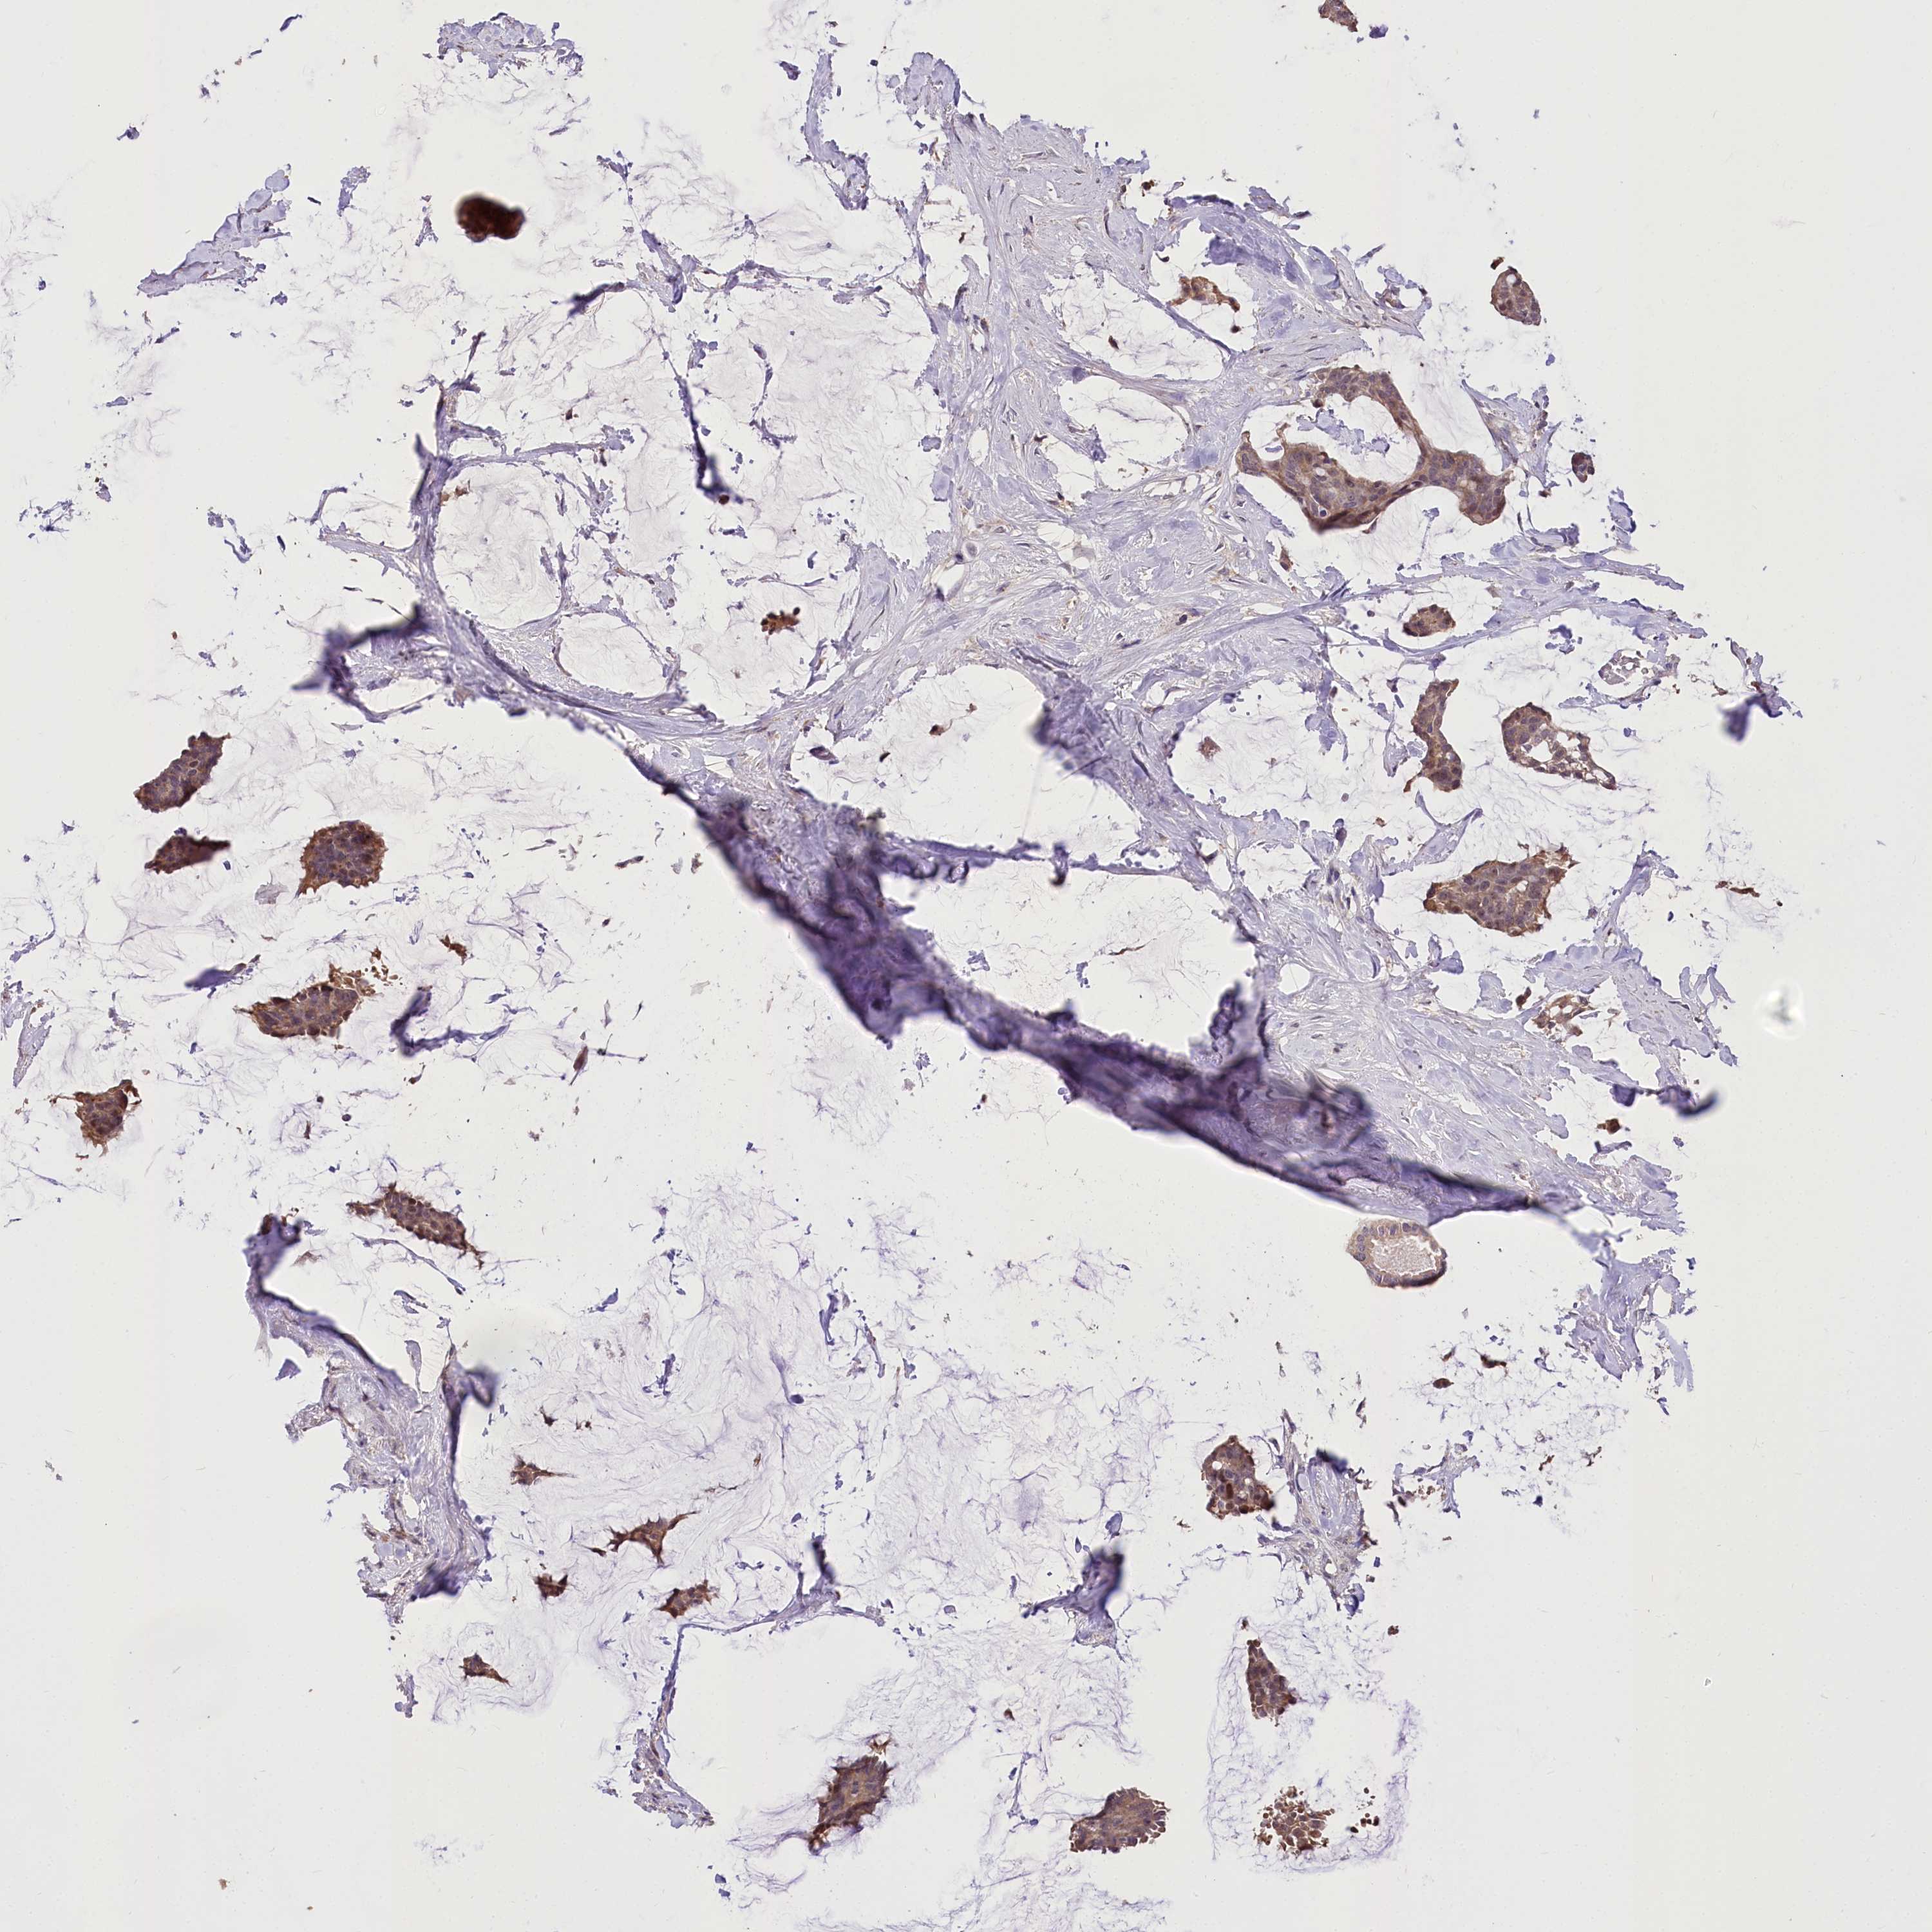

CANCER BREAST CANCER Show tissue menu

BRCA TCGA BRCA VALIDATION PROTEIN EXPRESSION